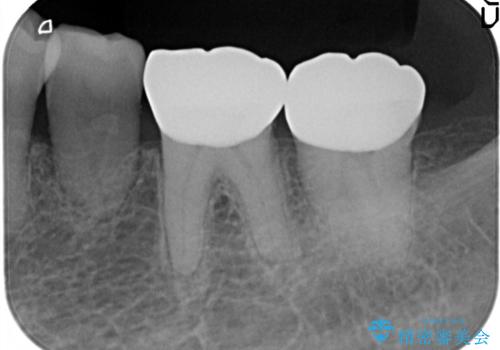

- 以前治療したところがしみて、アイスが食べられないから被せものの治療をしてほしいと来院された患者様です。

咬合が強く、歯牙にマイクロクラックが入っている状態でした。歯髄は保存可能と診断され、フルジルコニアクラウンによる治療を行いました。

咬合面に広範囲の修復物がある状態で中心に強い力が加わると歯牙は外方性の歪みが生じ、マイクロクラックができます。これを防ぐには、咬頭被覆するアンレー、もしくはクラウンによる治療が必要です。